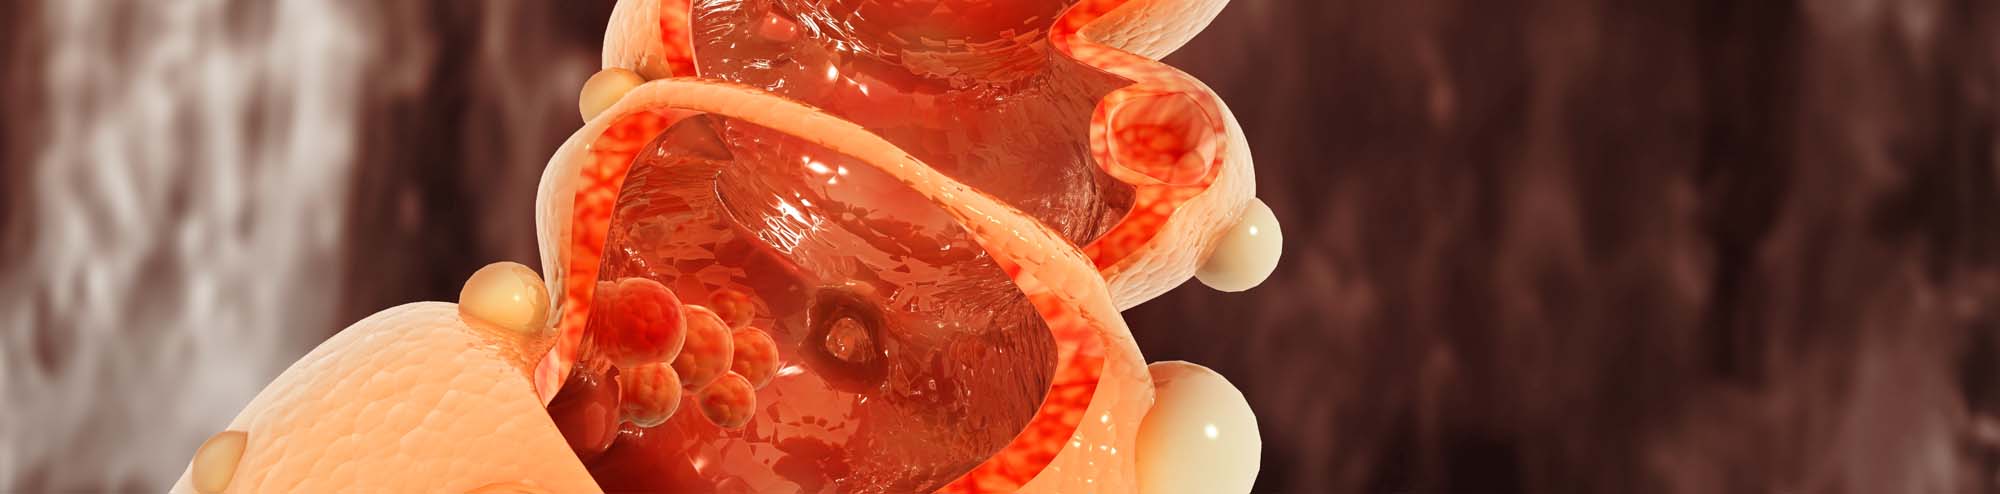

מחלה דלקתית כרונית של המעי Inflammatory Bowel Disease-IBD הינהן מונח כללית אשר כוללת בעיקר שתי מחלות עיקריות: קוליטיס

סרטן המעי הגס והחלחולת מהווה העילה השנייה בחשיבותה לתמותה הקשורה לתהליכי שאתיים בארצות הברית, כאשר בעולם נכון לשנת